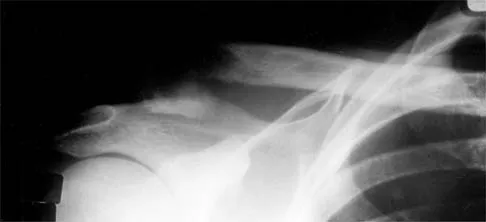

Figure 7 shows the radiograph of an otherwise healthy 65-year-old man who injured his right dominant shoulder while skiing 18 months ago. He did not seek treatment at the time of the injury. He now reports intermittent soreness when playing golf but has no other limitations. Examination reveals full range of motion and no tenderness, but he has slight pain with a crossed arm adduction stress test. He is neurologically intact. Initial management should consist of

Explanation

The radiograph shows a displaced type II distal clavicle fracture with nonunion. Because the patient's symptoms are minimal, the injury can be treated like a grade III acromioclavicular separation. Present management should consist of ice, anti-inflammatory drugs, activity modification, and perhaps physical therapy. If nonsurgical management fails to provide relief, the surgical options are varied with no uniformity in the literature regarding surgical treatment of this injury. Beaty JH (ed): Orthopaedic Knowledge Update 6. Rosemont, IL, American Academy of Orthopaedic Surgeons, 1999, pp 271-286.